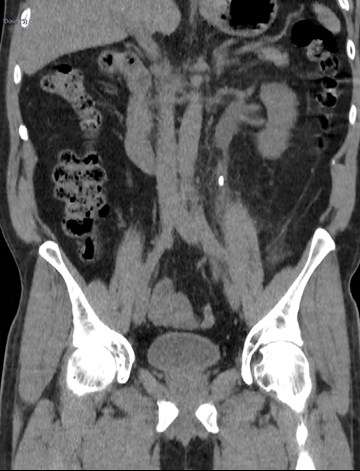

Figure 1.

1a) Describe Figure 1 and the acute urological diagnosis.

1a) This is a coronal reconstruction of an unenhanced low dose CT KUB in the soft tissue window which demonstrates a 9mm (craniocaudal length) left upper ureteric calculus with associated periureteric fat stranding and dilatation of the partially visualised renal pelvis.